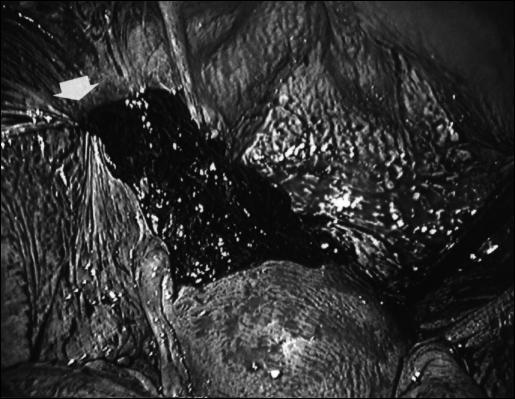

Hemoperitoneum after inguinal hernia repair, with the exception of laparoscopic herniorrhaphy, is extremely rare. No other case of hemoperitoneum after traditional open inguinal hernia repair has been reported in the English-language literature. A 39-year-old woman had undergone inguinal hernia repair with the Bassini repair technique. Lower abdominal pain and anemia occurred on postoperative day 1. Laparoscopy was performed and revealed hemoperitoneum caused as a complication of inguinal hernia repair. The abdominal cavity was thoroughly washed with saline solution, and the aspirated blood was processed and reinfused. Laparoscopy for hemoperitoneum as a complication after inguinal hernia repair was very useful for both diagnosis and treatment.

腹股沟疝修补术后出现腹腔积血极为罕见,但腹腔镜疝修补术除外。英文文献中未报道过传统开放性腹股沟疝修补术后出现腹腔积血的其他病例。一名39岁女性接受了采用巴西尼修补术的腹股沟疝修补术。术后第1天出现下腹部疼痛和贫血。进行了腹腔镜检查,发现腹腔积血是腹股沟疝修补术的并发症所致。用生理盐水彻底冲洗腹腔,并对吸出的血液进行处理后回输。腹腔镜检查对于诊断和治疗腹股沟疝修补术后作为并发症的腹腔积血非常有用。